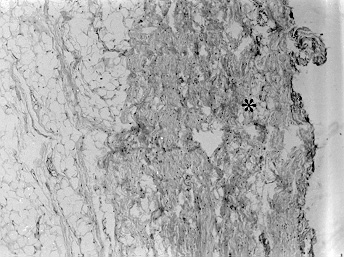

Microfotografia da membrana tireohióidea (*) de aspecto normal (H.E. X 85)